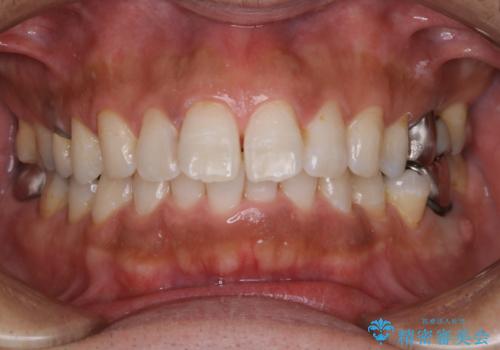

タバコやコーヒーによる着色落とし(PMTC)

- 着色を落としてほしいとのことで来院されました。

PMTC60分コースを行いました。

半年に一度クリーニングしているとのことでした。タバコとコーヒーの着色でした。

着色に厚みがあるため、エアーフローも使用して除去しました。